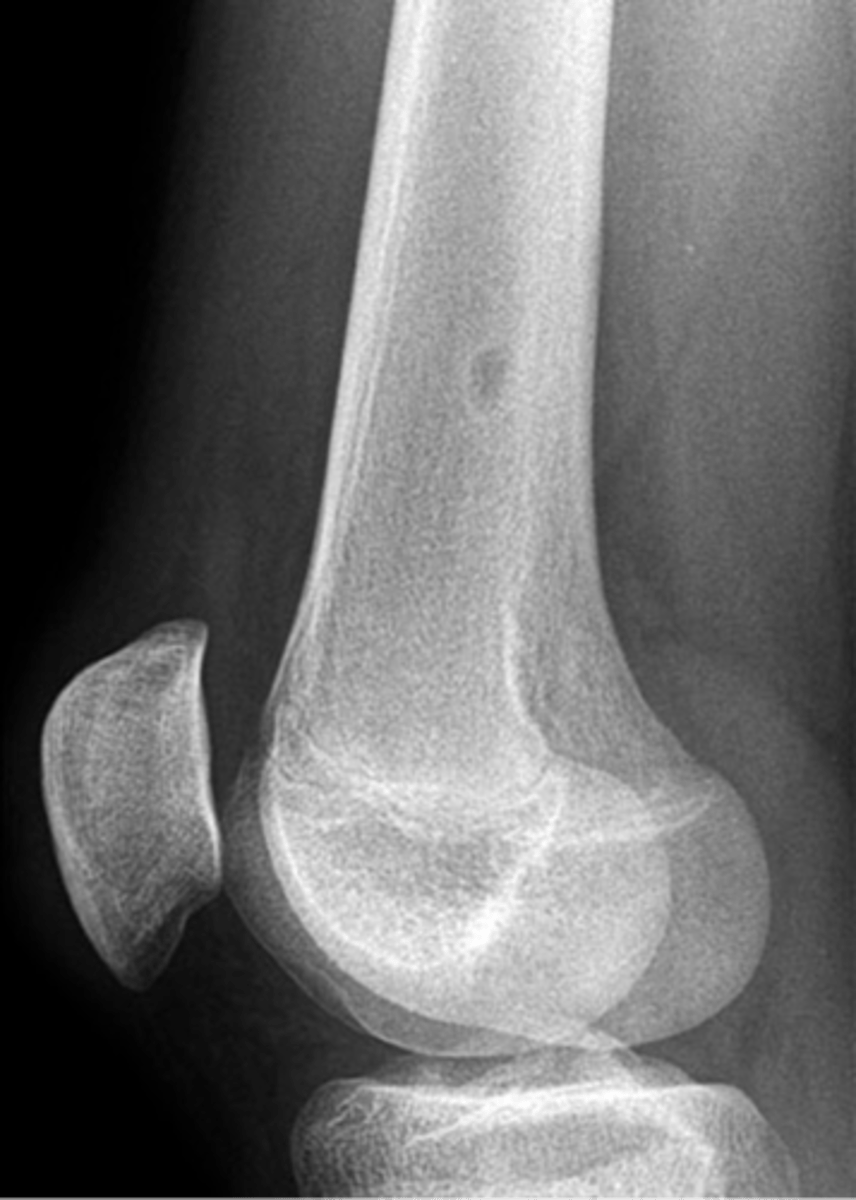

New cards

Simple bone cyst

- M:F, 2:1

- 3-14 y.o.

- Asymptomatic until fracture

- Proximal humerus (50%)

- Proximal femur (25%)

- Metaphyseal

- Migrate from physis with growth

<p>- M:F, 2:1</p><p>- 3-14 y.o.</p><p>- Asymptomatic until fracture</p><p>- Proximal humerus (50%)</p><p>- Proximal femur (25%)</p><p>- Metaphyseal</p><p>- Migrate from physis with growth</p>

62

- Mildly expansile

- Geographic

- Pseudoloculated

- Central

- 30-40% recurrence

State the radiographic features of simple bone cyst

<p>State the radiographic features of simple bone cyst</p>

63

Pathologic fracture

ID radiographic feature of simple bone cyst indicated by the top arrow

<p>ID radiographic feature of simple bone cyst indicated by the top arrow</p>

64

Fallen fragment sign

ID radiographic feature of simple bone cyst indicated by the bottom arrow

<p>ID radiographic feature of simple bone cyst indicated by the bottom arrow</p>

65

Fallen fragment sign (10%)

- Cortex broke off

- Pathognomonic

<p>- Cortex broke off</p><p>- Pathognomonic</p>